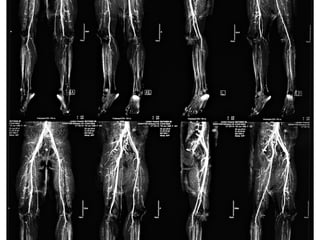

ชายไทยอายุ 21 ปี ถูกยิง 1 ครั้ง ที่ขา 2 ขา

ก่อนมาโรงพยาบาล 2 ชั่วโมง

ขาขา

ขวาขวา

ซ้ายซ้าย

Intraoperative Rx